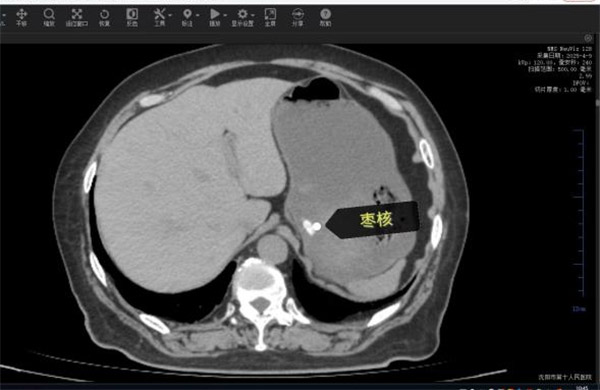

63岁的康阿姨因突发"刀绞般"的剧烈腹痛被深夜紧急送往沈阳市第十人民医院(沈阳市胸科医院)。短短数小时内,她已出现高热、腹肌强直等弥漫性腹膜炎症状,CT检查显示其腹腔内游离气体,高度怀疑消化道穿孔。追问病史时家属猛然回忆:今天上午康阿姨吃粽子时误将两颗枣核吞下!沈阳市第十人民医院(沈阳市胸科医院)普外科任庆华主任团队火速会诊,判断枣核尖端已刺穿小肠,必须立即手术。

凌晨的手术室里,任庆华主任与刘晓斌副主任医师打开腹腔时,眼前的场景令人心惊:大量浑浊脓液涌出,两枚长达3cm的尖锐枣核分别嵌顿在幽门处与回肠段,其中远端小肠已形成两处直径0.8cm的穿孔,两处约10cm及5厘米肠管因缺血呈黑紫色。医疗团队当机立断,行"胃切开异物取出术"完整取出胃内枣核后,针对坏死肠段实施精准的"小肠多节段部分切除术",同时分解患者既往腹部手术形成的致密粘连。凭借丰富的临床经验,团队在确保彻底清除感染灶的前提下,最大限度保留了健康肠管。